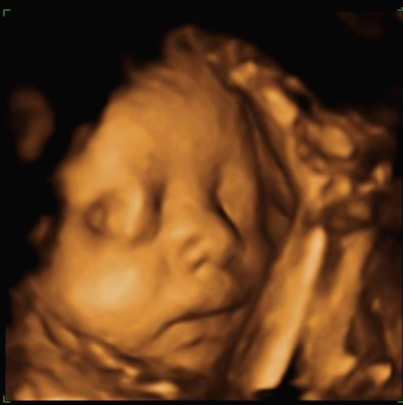

그리고 초음파 봐주시는 분께서 13주차가 되면 정확히 알 수 있으니 다음 주에 오라고 하셔서 일주일 뒤 다시 방문을 했습니다. (위에 사진은 12주 차 때 아들이라고 보여주신 초음파 사진이에요~ 화살표 보면 툭 튀어나와있는 부분을 보여주면서 아들이라고 하셨어요~)

24주 차에 다시 사설로 초음파 검사를 받으러 갔는데 초음파를 보시더니 정밀 초음파 검사 때 성별 딸이 었냐 아들이 었냐 물어보시길래 딸이라고 말을 하니 미안하다고 지금 보니 딸이라고 하길래 이때는 정밀 초음파 검사 후 한 달 뒤여서 상관없다고 ㅋㅋㅋㅋㅋ 아들인지 딸인지 뭐가 중요하냐고 아이만 건강하면 된다고 하니 ㅎㅎ 그때서야 웃으시더라고요 ㅎㅎ 많이 미안했던 모양... 워낙 아이 건강상태를 꼼꼼하게 잘 봐주시고 만족할만하게 아이 얼굴 초음파 사진을 찍어주셔서 다 용서가 됐어요 ㅎㅎ

내 뱃속에 이렇게 사랑스러운 아이가 있다니 >. < 이렇게 이쁜 아이를 보면 성별반전은 중요하지 않아요~

입체 초음파 사진은 항상 만족스러워요! 사진 보면 벌써 태어난 아기처럼 어찌 이리 이목구비 뚜렷하고 아이 얼굴이 선명하게 잘 보이는지~ 제아이라 이렇게 사랑스러운 걸까요~? ㅋㅋㅋ